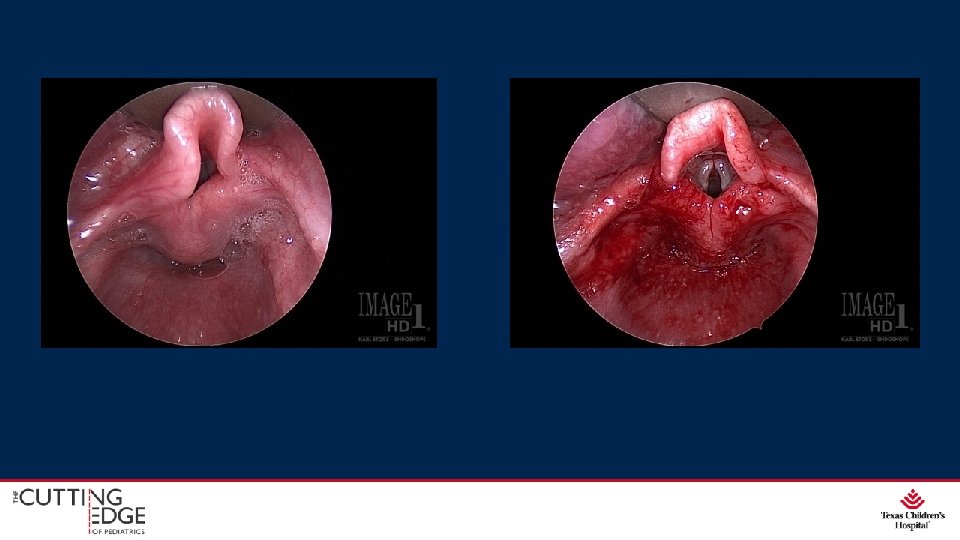

Flexible Fiberoptic Laryngoscopy • In-office • No sedation required • Gives a good view from nasal cavity to vocal folds

Direct Laryngoscopy and Bronchoscopy

3 Basic Supraglottic Abnormalities • Elongated, tubular epiglottis that collapses medially • Short aryepiglottic folds • Bulky, redundant mucosa overlying arytenoids that collapses anteriorly

Surgical Management Supraglottoplasty • Release aryepiglottic folds • Trim redundant arytenoid tissue • +/- epiglottopexy